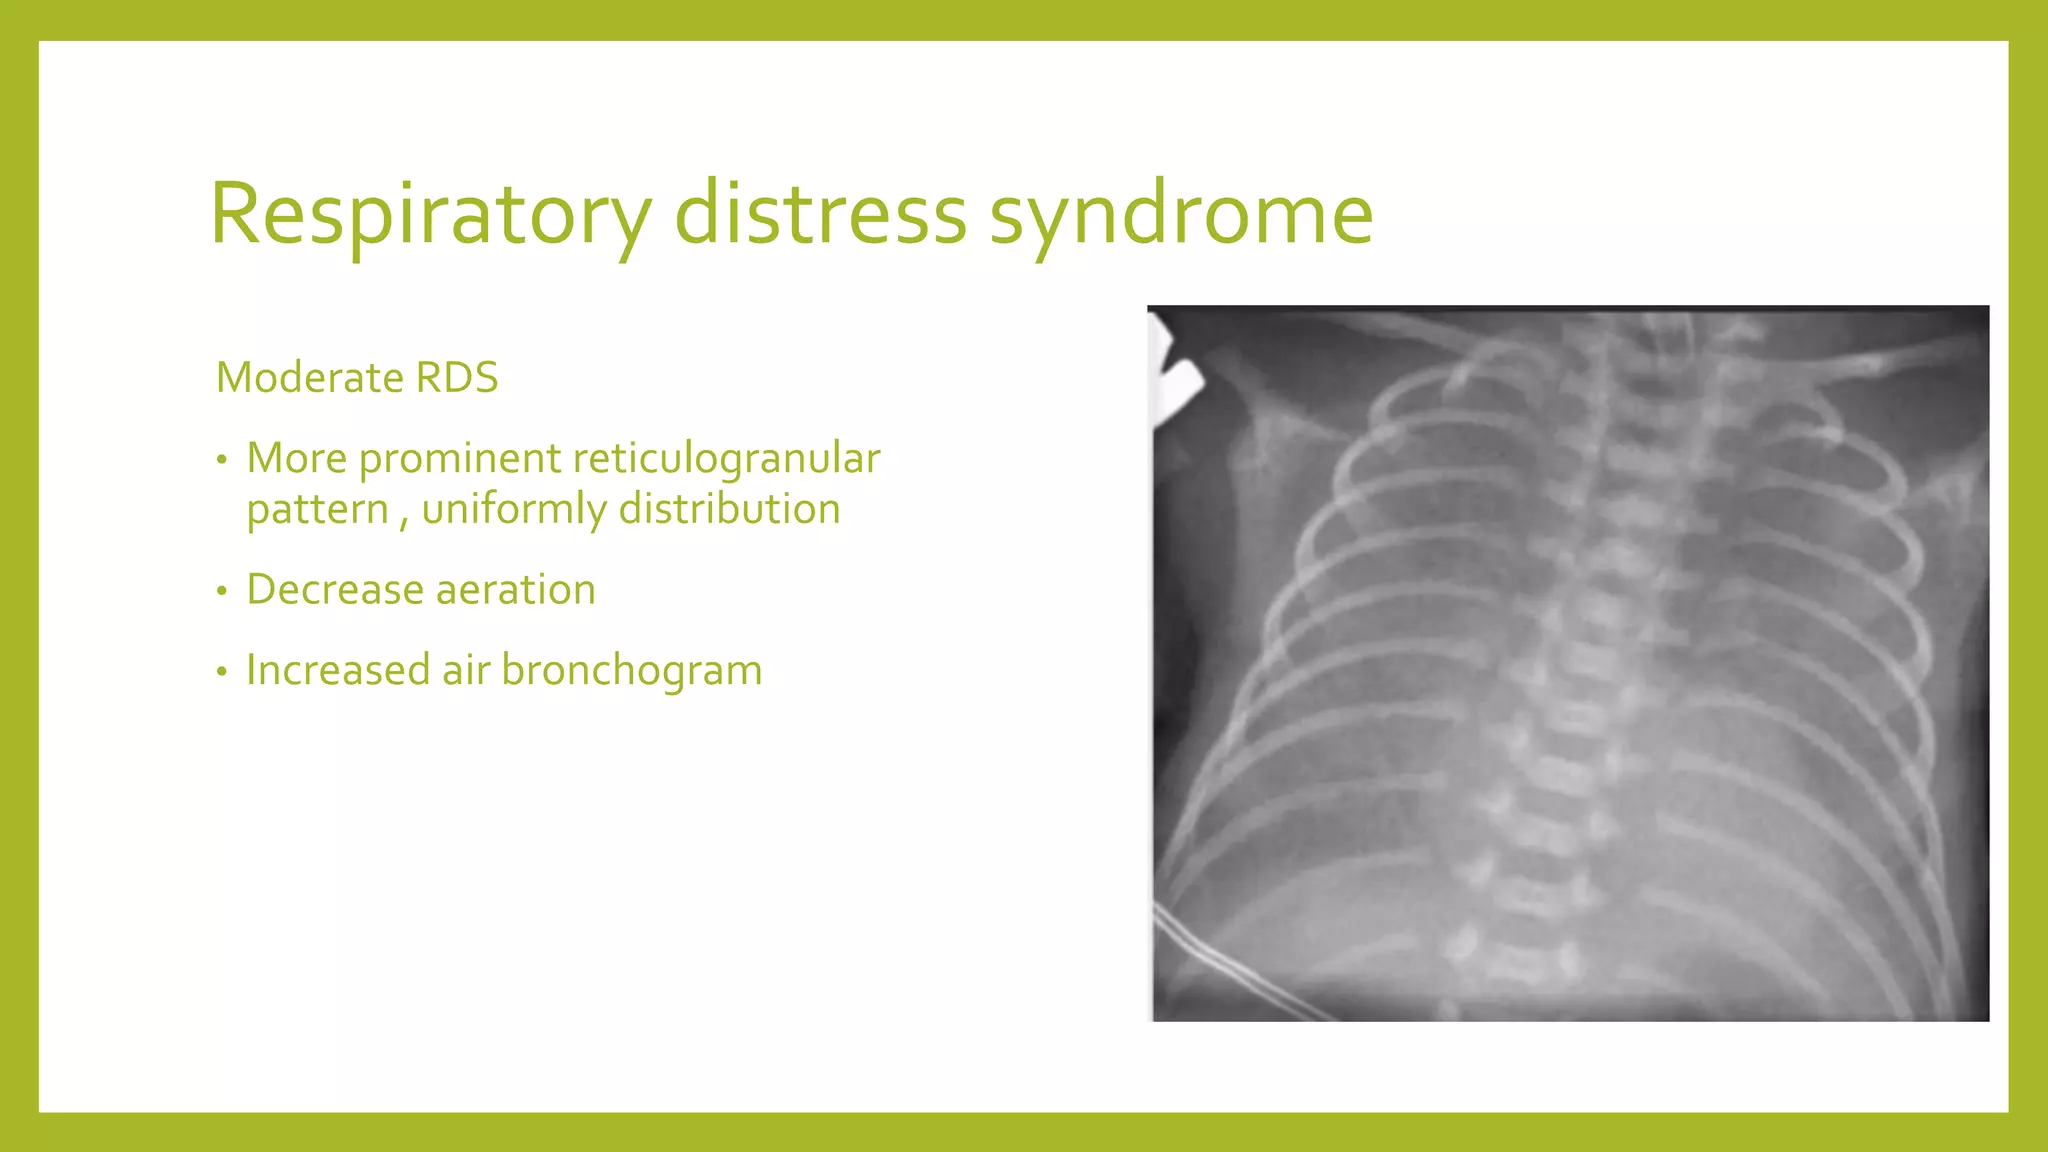

The document provides guidance on approaching and interpreting chest x-rays (CXR). It outlines steps to check the name, date and quality of the film, systematically scan the CXR looking for abnormalities, and determine if the lungs appear too white or black. Specific signs are described to help localize abnormalities, including the cardiac silhouette sign and pleural effusion signs. Examples are given of respiratory distress syndrome, tetralogy of fallot, transposition of great arteries, and total anomalous pulmonary venous return. The take home message is to summarize positive findings, compare to prior CXRs if available, and confirm findings with a radiologist.